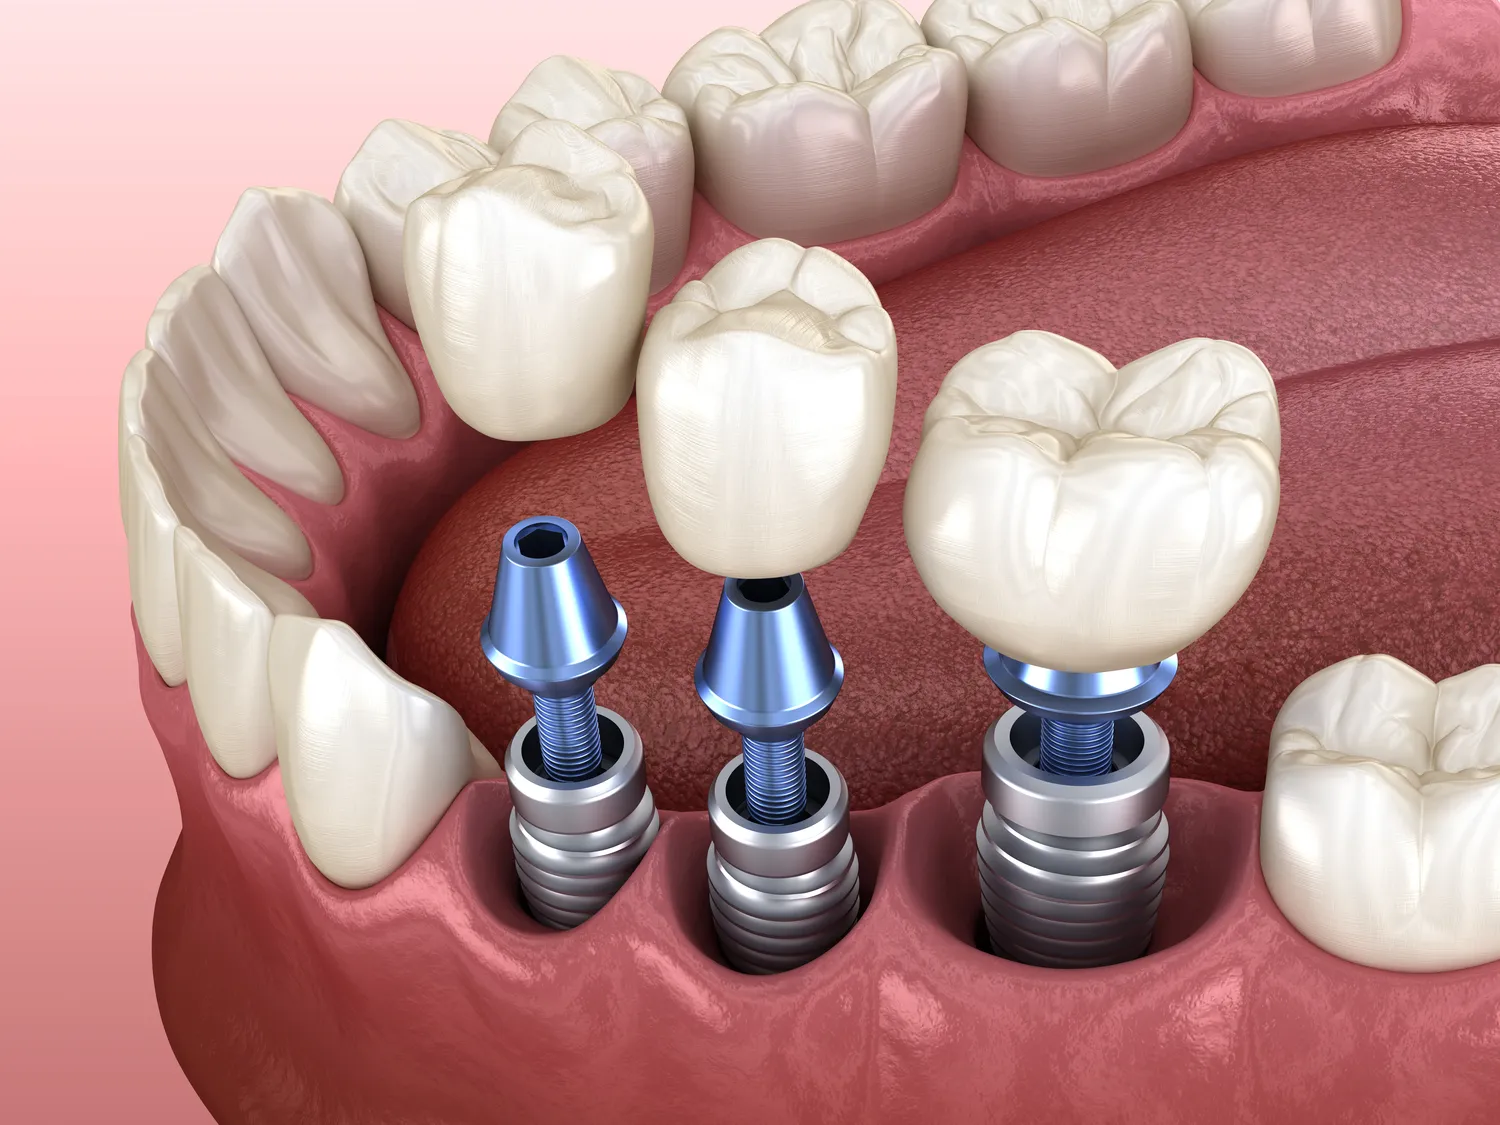

- Implantologia stomatologiczna, pozwalająca na trwałe uzupełnienie braków zębowych.

Warto podkreślić, że stomatolog często współpracuje z innymi specjalistami, takimi jak ortodonci, chirurdzy szczękowo-twarzowi czy protetycy, aby zapewnić pacjentowi kompleksową opiekę. Jego wiedza i umiejętności pozwalają na przywrócenie pacjentowi funkcji żucia, mowy oraz pięknego uśmiechu.

Wiek senioralny to kolejny okres, w którym rola stomatologa jest nieoceniona. Z wiekiem często pojawiają się specyficzne problemy związane z jamą ustną, takie jak suchość w ustach (kserostomia), zwiększone ryzyko próchnicy korzeni, choroby przyzębia czy zużycie uzębienia. Stomatolog potrafi dobrać odpowiednie metody leczenia i profilaktyki, aby zapewnić seniorom komfort życia, możliwość prawidłowego odżywiania się i utrzymania dobrej jakości życia. Protezy zębowe, implanty czy specjalistyczne pasty do zębów to tylko niektóre z rozwiązań, które mogą być zaproponowane.

- Chirurgia stomatologiczna – obejmuje zabiegi takie jak ekstrakcje zębów (w tym ósemek), resekcje wierzchołka korzenia, usuwanie torbieli czy wszczepianie implantów.

- Implantologia – specjalistyczna dziedzina chirurgii stomatologicznej, poświęcona chirurgicznemu wszczepianiu implantów zębowych, stanowiących nowoczesne uzupełnienie brakujących zębów.